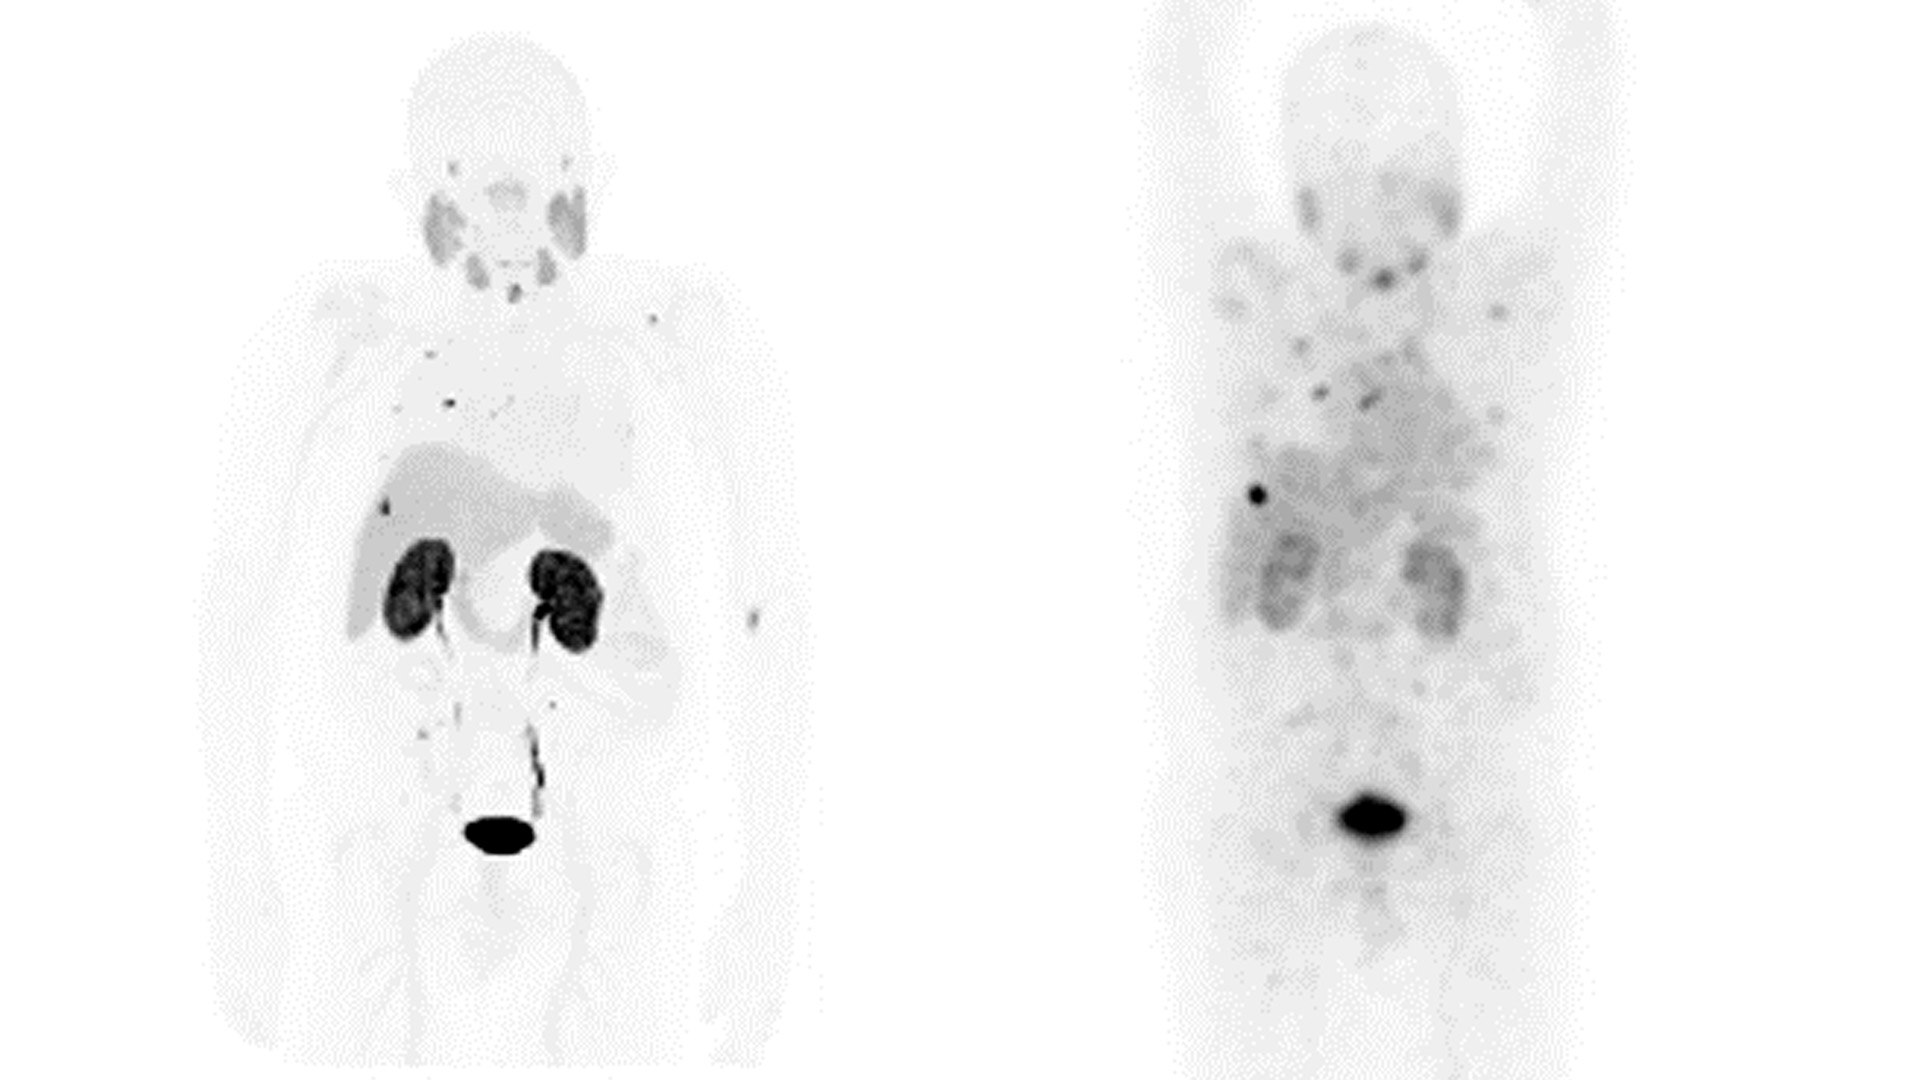

TANI

GE, benzersiz hassasiyet ve tanısal güven sağlayan çözümlere öncülük etmektedir.

Teranostik odaklı tanısal görüntüleme çözümlerinden oluşan özel portföyümüz, günümüzde ve gelecekte klinisyenlerin ve hastalarının ihtiyaçlarını karşılamak için özel olarak tasarlanmıştır.